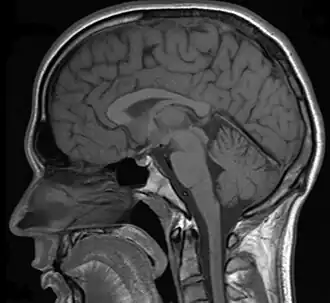

In a case of misdiagnosed depression recounted in Newsweek, a writer received treatment for depression for years; during the last 10 years of her depression the symptoms worsened, resulting in multiple suicide attempts and psychiatric hospitalizations. When an MRI finally was performed, it showed the presence of a tumor. However, she was told by a neurologist that it was benign. After a worsening of symptoms, and upon the second opinion of another neurologist, the tumor was removed. After the surgery, she no longer had depressive symptoms.[28]

In addition to pituitary tumors, tumors in various locations in the central nervous system may cause depressive symptoms and be misdiagnosed as depression.[28][69]